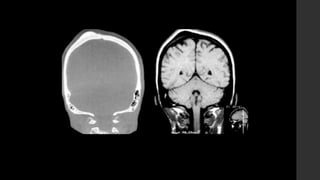

Osteoblastoma.

• RX 

Lesiones predominantemente líticas con un anillo esclerótico

reactivo periférico.

Tendencia a ser expansivas.

Presencia de calcificaciones internas.

Puede presentar masa de tejidos blandos asociada.

Tienen crecimiento rápido demostrado por expansión cortical,

algunas veces con destrucción cortical.

Puede presentar quiste óseo aneurismático en 20%.

• TC 

 Lesiones predominantemente líticas similares a la radiografía.

 La matriz interna se demuestra mejor en TC.

• IRM 

 Características no específicas.

 T1: Señal intermedia con áreas de menor intensidad de señal que

corresponden a focos de calcificación.

 T1+C: Realce ávido del tumor con realce asociado de tejidos blandos

periféricos.

 T2: Señal intermedia a baja con focos de calcificación hipointensos. Puede

haber señal alta debido a edema de la médula ósea y tejidos blandos

periféricos (fenómeno de llamarada”).